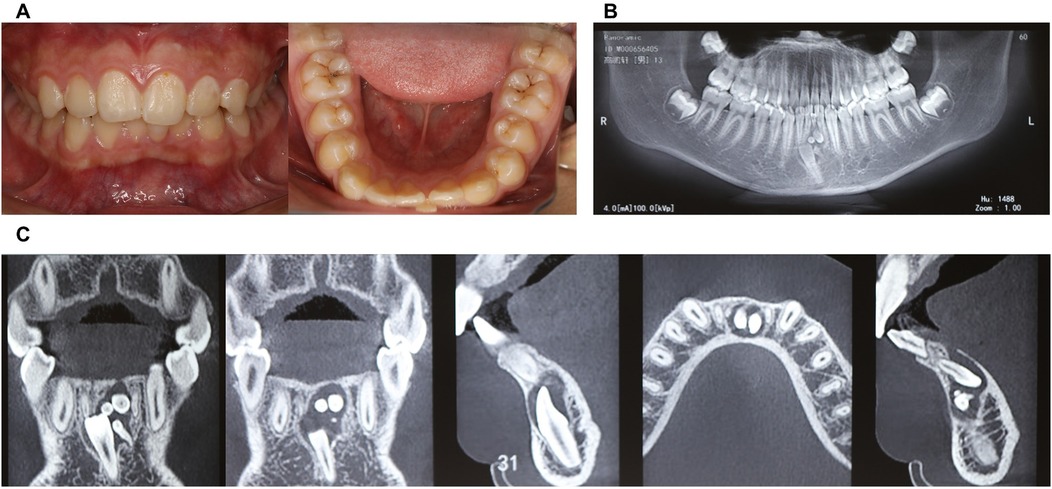

Intraoral examination revealed retained primary tooth 71 and unerupted permanent tooth 31 (Figure 1A). CBCT imaging identified a compound odontoma adjacent to tooth 31 (Figures 1B,C). After discussing the treatment plan, surgical procedure, and associated risks/benefits with written instructions, the guardians consented to autonomous robotic extraction of the compound odontoma (Yakebot; Yakebot Technology Co., Ltd., Beijing, China).

Figure 1. Physical and CBCT examination of compound odontoma. (A) Photos of intraoral view; (B) CBCT examination (overall view); (C) CBCT examination (location of compound odontoma in the anterior mandibular region, including sagittal, coronal, and axial planes).